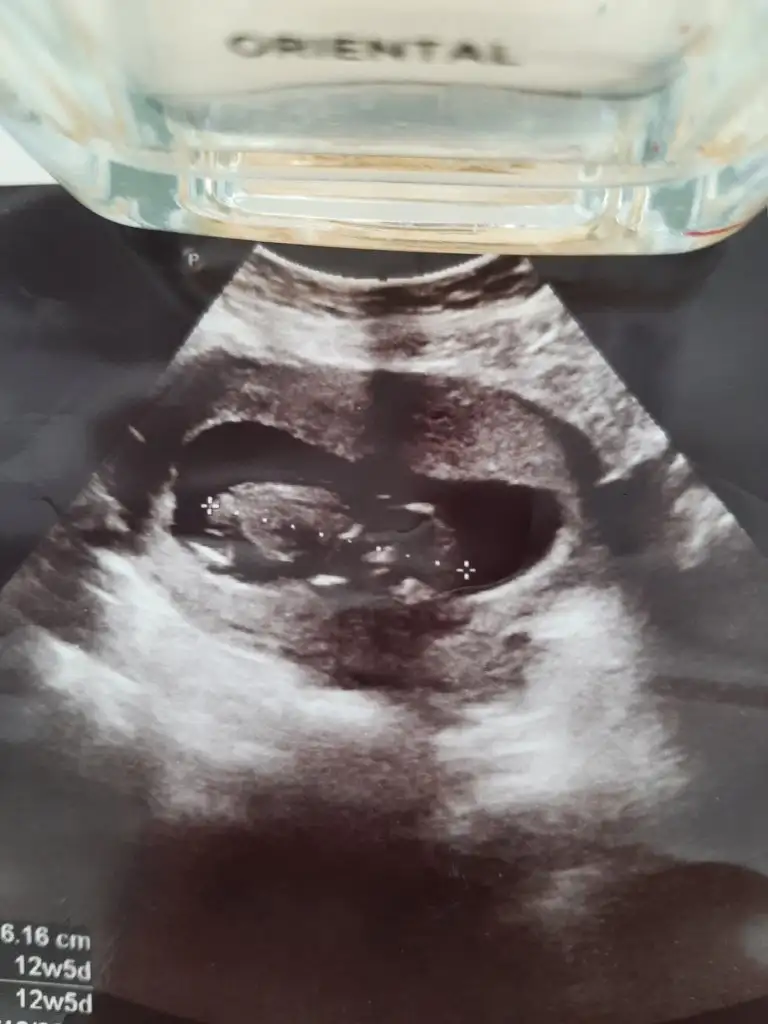

Merhaba nursu 11 haftalik atmistim prenses gibi demistin bugün 13 +2 hafta olduk özel hastanede doktor %90 erkek dedi son foto attım yeniden baksana

12+5 günlük karından çekildi yorum yapabilirmisiin Pasha22 Pasha22